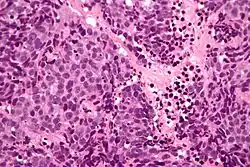

| Micrograph of a sinonasal undifferentiated carcinoma. H&E stain. | |